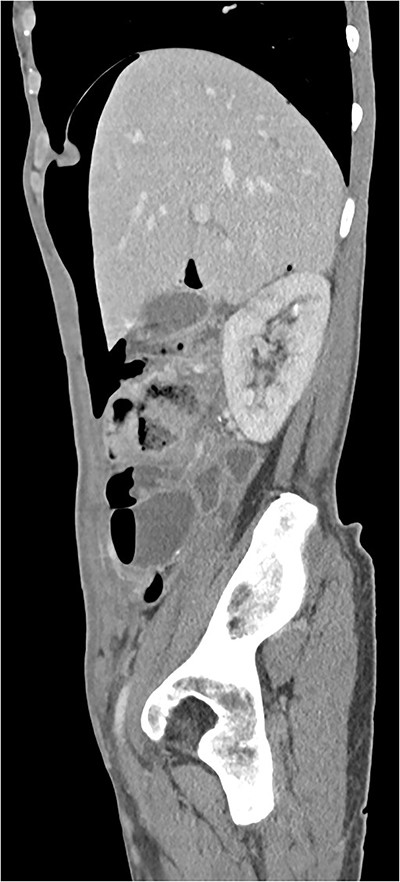

A 55-year-old woman was being followed in a gynecology consultation for a large abdominal mass, likely of adnexal origin (370 mm in its largest dimension). She underwent a hysterectomy, bilateral adnexectomy, and segmental enterectomy due to an iatrogenic perforation of a small bowel loop. On the seventh postoperative day, due to the absence of intestinal transit since surgery, an abdominal X-ray was requested, and general surgery was consulted, suspecting pneumoperitoneum. In this context, the patient underwent a CT scan, which revealed “pneumoperitoneum in the free cavity, significant for one week postoperative, with about 4 cm anteroposterior diameter in the epigastric region. There is also a significant amount of retroperitoneal air in the left pelvic cavity, extending to the presacral space. There are no gas bubbles immediately adjacent to the surgical suture lines.” (Figs 3 and 4). Blood tests showed no significant alterations, and clinically, the patient was hemodynamically stable with only mild tenderness on abdominal palpation, without guarding. Based on the clinical, laboratory, and imaging findings, it was decided to keep the patient on a nil-by-mouth diet with clinical observation. The next day, the patient resumed intestinal transit, allowing for the reintroduction of an oral diet. Blood tests showed no increase in inflammatory markers. The patient continued to progress favorably during the remainder of her hospital stay and was discharged on the tenth postoperative day.